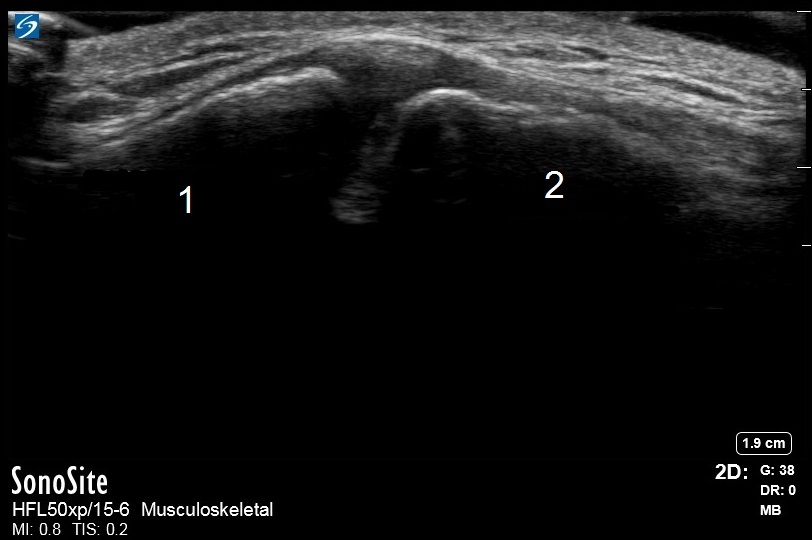

肩の通常の肩関節鎖骨関節のイメージ

肩峰

鎖骨